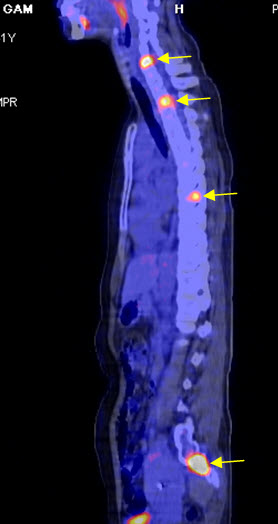

Hình 6. Bệnh nhân Lê T. H. G., nữ, 41 tuổi. Chẩn đoán: Ung thư vú đã điều trị cách đấy 8 năm. Hiện tại bệnh nhân đi khám lại thấy có chỉ điểm ung thư (CA 15-3) tăng. Trên hình PET/CT cho thấy tổn thương xương nhiều ổ tại cột sống, xương cánh tay (các mũi tên). (Nguồn: Mai Trọng Khoa – Trung tâm Y học hạt nhân và ung bướu – BV Bạch Mai)